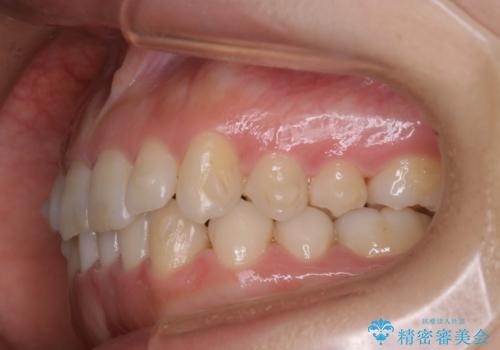

上顎の真ん中の歯の角度が、内側に傾いており、またその隣の歯が、唇側にずれてしまっていました。

上顎の前歯の傾きを改善することで、がたつきを治すためのスペースを確保しました。

また、それだけではがたつきを改善するスペースが不足していたため、歯の側面を削りがたつきを改善しました。